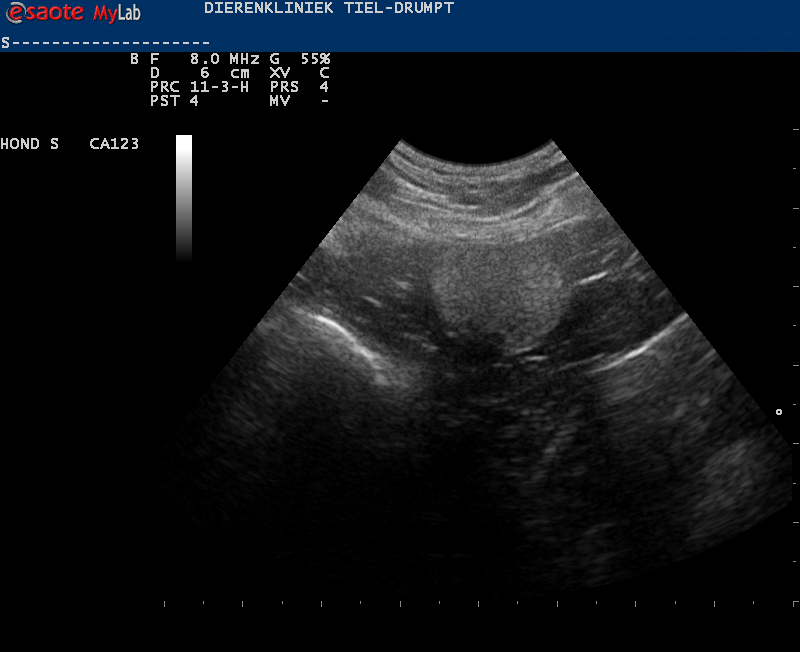

In dat geval kan er gezocht worden met een echo en in de meeste gevallen is het mogelijk om hem daarmee te localiseren. In principe zullen de meeste testikels ergens tussen de nier en het scrotum liggen. Heel soms zijn ze niet aangelegd.